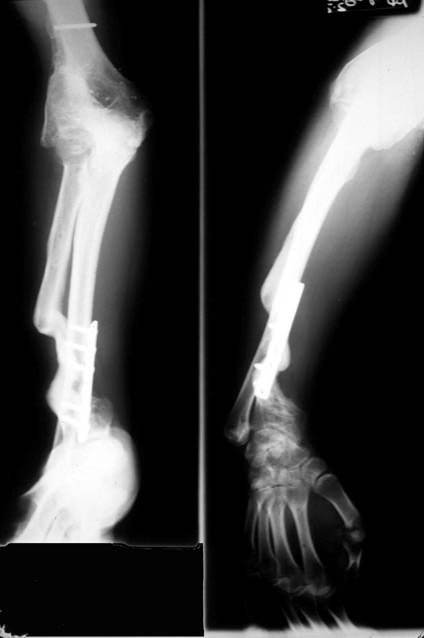

E.R. is a 26 year old male lifeguard who had a severe, unfortunate accident the first time he ever mounted a motorcycle. He was in a coma for many months with head trauma and had fractured his right elbow and forearm at the time of injury. He developed a condition called Heterotopic Ossification which meant that multiple joints «froze-up» due to deposits of calcium in the joint capsules. He was not able to walk until both hips were operated on by an internationally known hip surgeon who then referred him to Dr. Badia to address the stiff Right elbow and deformed forearm. In fact, at the initial visit, the patient stated that he had not moved the right elbow AT ALL for nearly 4 years and was unable to feed or groom himself with that hand. After a series of 3 operations to reconstruct both the elbow and forearm, this young man has gone back to swimming, work and a normal lifestyle.

The pictures depict the application of the dynamic external fixator, which stabilized and provided early motion to the rigid elbow after aggressive release of the capsule and bone excision.